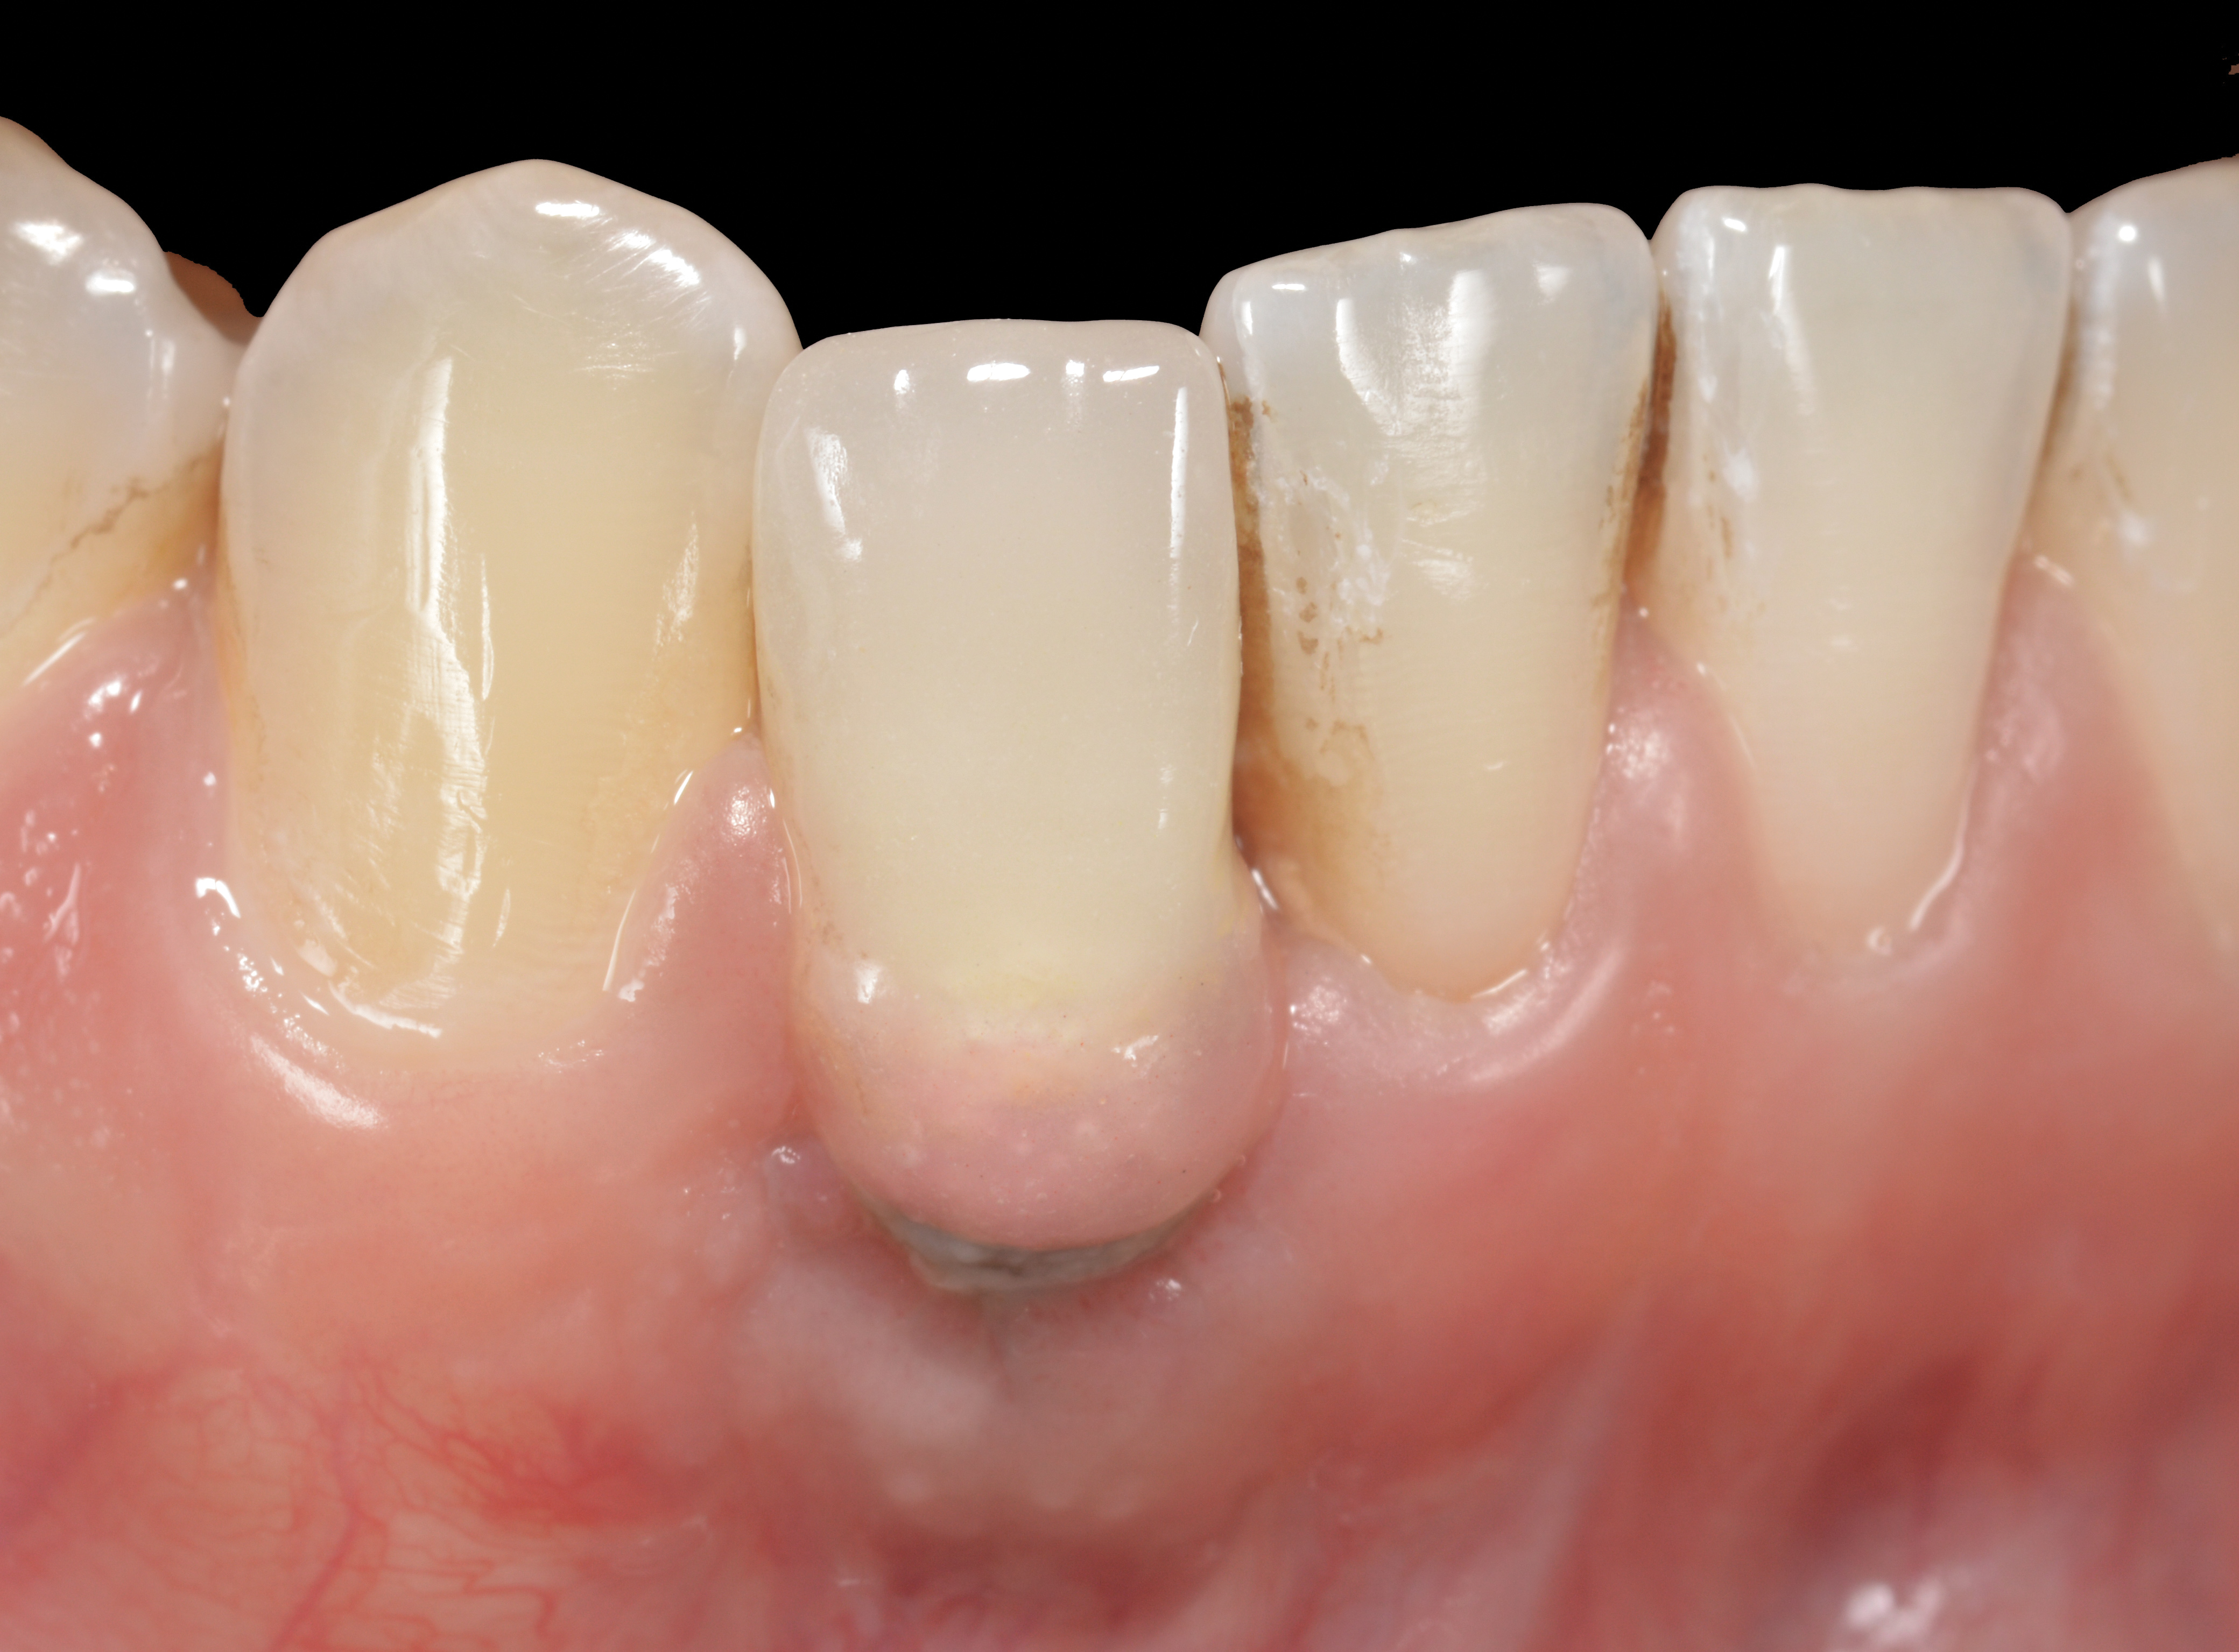

The following case report provides an example of this case scenario: A 28-year-old white female patient presented with her maxillary right lateral incisor significantly longer than the contralateral tooth following restoration of an existing crown that was 10 years old (Figure 3). The patient was dissatisfied with the esthetic appearance of the restoration due to the increased length, recession of the gingival tissues, and discoloration of the surrounding mucosa (Figure 4). Similar to case scenario No. 1, the first step in treatment was to decoronate the healthy implant by placing a flat surgical cover screw and employing a provisional resin-bonded-retained (RBR) prosthesis as a transitional fixed restoration (Figure 5 and Figure 6). The gingival augmentation in situ was allowed to take place for 2 to 3 weeks and was evaluated after that time (Figure 7).

It was determined that additional augmentation was required to increase the soft-tissue volume, so a subepithelial connective tissue graft was acquired from the palate (Figure 8),23,24 placed, and allowed to mature for at least 3 months. Second-stage implant undercovering surgery with a palatal-biased incision was performed after tissue maturation to further thicken the labial soft tissues. In addition, a flat contoured healing abutment was placed to allow the soft tissues to mature without risk of recession, and the RBR replaced (Figure 9). After 4 to 6 weeks of healing, a flat contoured screw-retained provisional restoration was inserted (Figure 10) with the proper submergence profile to restoratively sculpt the soft tissues. An implant-level impression was made and the definitive cement-retained metal-ceramic restoration fabricated and inserted (Figure 11 through Figure 13). The final esthetic outcome to restore the proper length and proportion of the right lateral incisor to match that of the contralateral incisor was accomplished using the treatment steps outlined above, where the mucosal tissues were augmented after implant decoronation (Figure 14).

Fig 9. After 3 months of healing, the implant was uncovered. A crestal incision was made with a palatal bias and rolled to the labial side to increase the soft tissue to the facial aspect.

Figure 9

Fig 10. A flat submergence profile was created for the screw-retained provisional crown. Acrylic resin was strategically added to the cervical aspect of the provisional restoration to accomplish this goal.

Figure 10